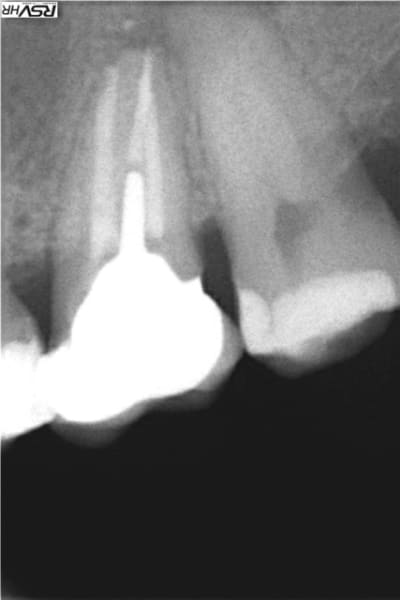

Il n'y a pas que la technique d'obturation qu'il faut revoir mais aussi l'alésage. Sur la radio, l'apex est défoncé: la racine à une courbure mésiale et l'obturation est rectiligne et perfore la racine à la courbure apicale.

La pâte est partie droite dans l'os (qui a dû être aussi alésé ...) et a fusé en nappe quand elle a atteint le sinus.

En plus c'est sur-alésé et certainement avec des instruments trop rigides qui ont tout défoncé.

ci-joint un cas de dépassement de pâte canalaire après compactage mac spadden

heureusement pour moi et le patient la pâte du sealite regular

s'est dissous naturellement de fin 2012 (dépassement)

à fin 2015 trace disparue

Je te donne mon interprétation "airylis"

tu as une 14 avec 2 racines la palatine plus longue qui donne donc l'impression d’être devant la racine vestibulaire

le cône de gutta ne suit pas la courbure donc alésage légèrement droit et faux canal et donc la pâte a fusé

et suivi la courbure de ton sinus d’où l'arc de cercle;

la membrane de schneider a sans doute empêché la pâte de fuser dans le sinus;donc pour moi pas d'effraction de la membrane sinusienne sion image verticale....

Oui la pate ne semble pas être dans le sinus mais entre la membrane et l'os , mais d'une part je mets très peu de pate et d'autre part cette image ne ressemble pas à un dépassement , c'est "canalisé" ... J'arrive maintenant à positiver car le scanner du sinus fait quelques jours apres révèle plusieurs anomalies mais ne parle pas de ma pate et le patient est content de ne plus avoir ses douleurs sinusales , mais j'ai mis plusieurs jours à retrouver le sommeil aprés ce traitement et à oser faire des endos ...

Je pense que tu as fait ce qu'on appelle un zipping de ton apex. en gros tes limes de mise en forme ont peu à peu dévier la courbure. En gros apex explosé...

Tu as sûrement fait une erreur de calibration de ton maître cône de gutta. Toujours vérifier qu'on aune bonne butée. Il semble que ton dépassement soit un mélange de gutta et de pâte, donc peu probable que cela se résorbe.

Même chose que M2, faux canal avec dépassement (ne suit pas la courbure apicale) et fusée de pâte. On le voit bien sur la radio